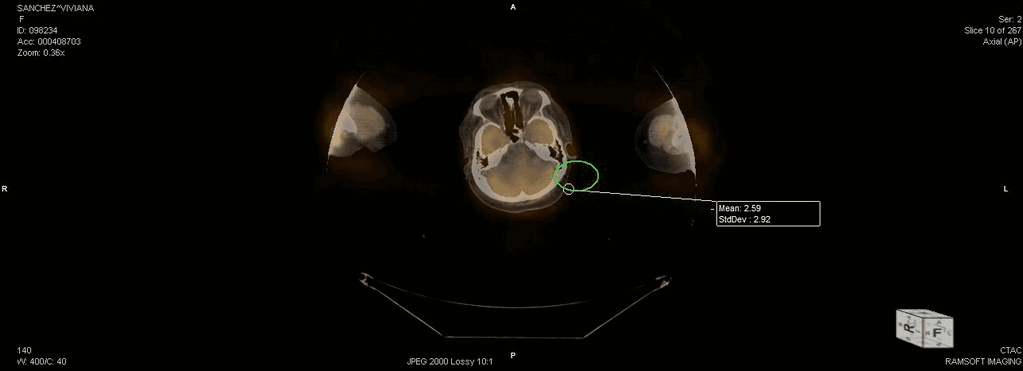

The following image shows an ROI tool being applied in the MPR mode.

Clicking on the "+" sign expands the ROI statistics like the area of the ROI and the Mean and Standard Deviation values of the pixel intensities.